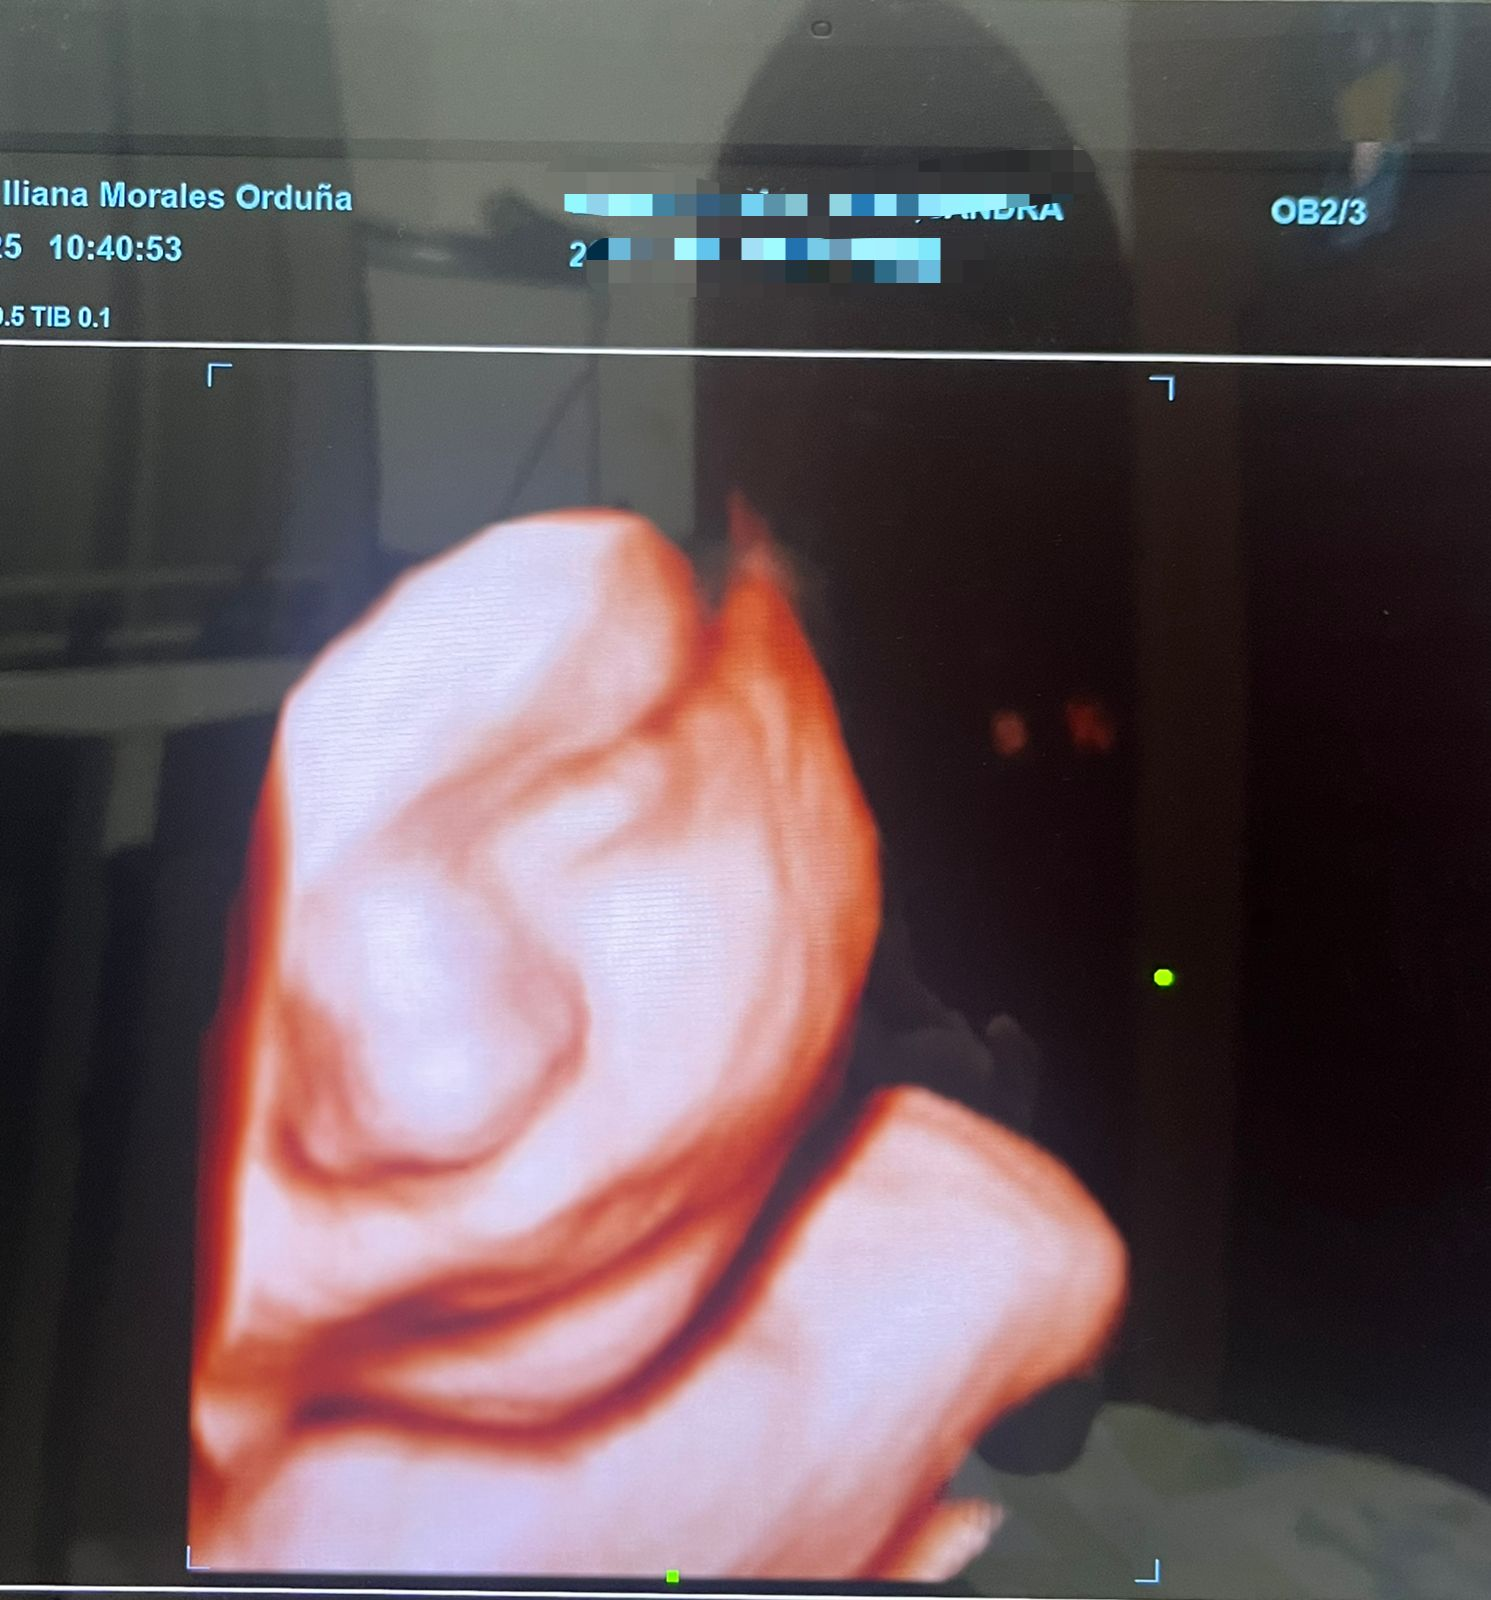

• Ultrasonidos Obstétricos (Embarazo)

• Ultrasonidos 3D y 4D